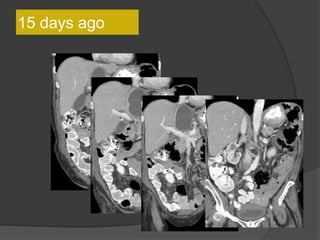

Case 1: 64F, abdominal distention, pain, h/o

SBO

Axial CT images

15 days ago

This lesion is larger compared to the CT 15 days

ago

• Multilobulated thick-walled cystic lesion in the lesser sac and extending along the

adjacent peritoneal spaces and gastrohepatic ligament. Cystic lesion in the left

hemipelvis

• Minimal ascites, omental and mesenteric thickening

Present exam 15 days ago

Increased size

Case 1 Diagnosis: Recurrent metastatic disease

with mucinous ovarian tumor